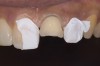

Figure 2  Supraeruption of a lower incisor due to wear on the palatal of the upper anterior.

Figure 2

Acid dissolves the palatal enamel of upper anteriors, thus exposing the underlying dentin. This makes teeth appear higher in chroma and leads to hypersensitivity as well as supraeruption of opposing incisors. Clinically, this restricts the space needed to restore lost palatal tooth structure (Figure 1 and Figure 2).